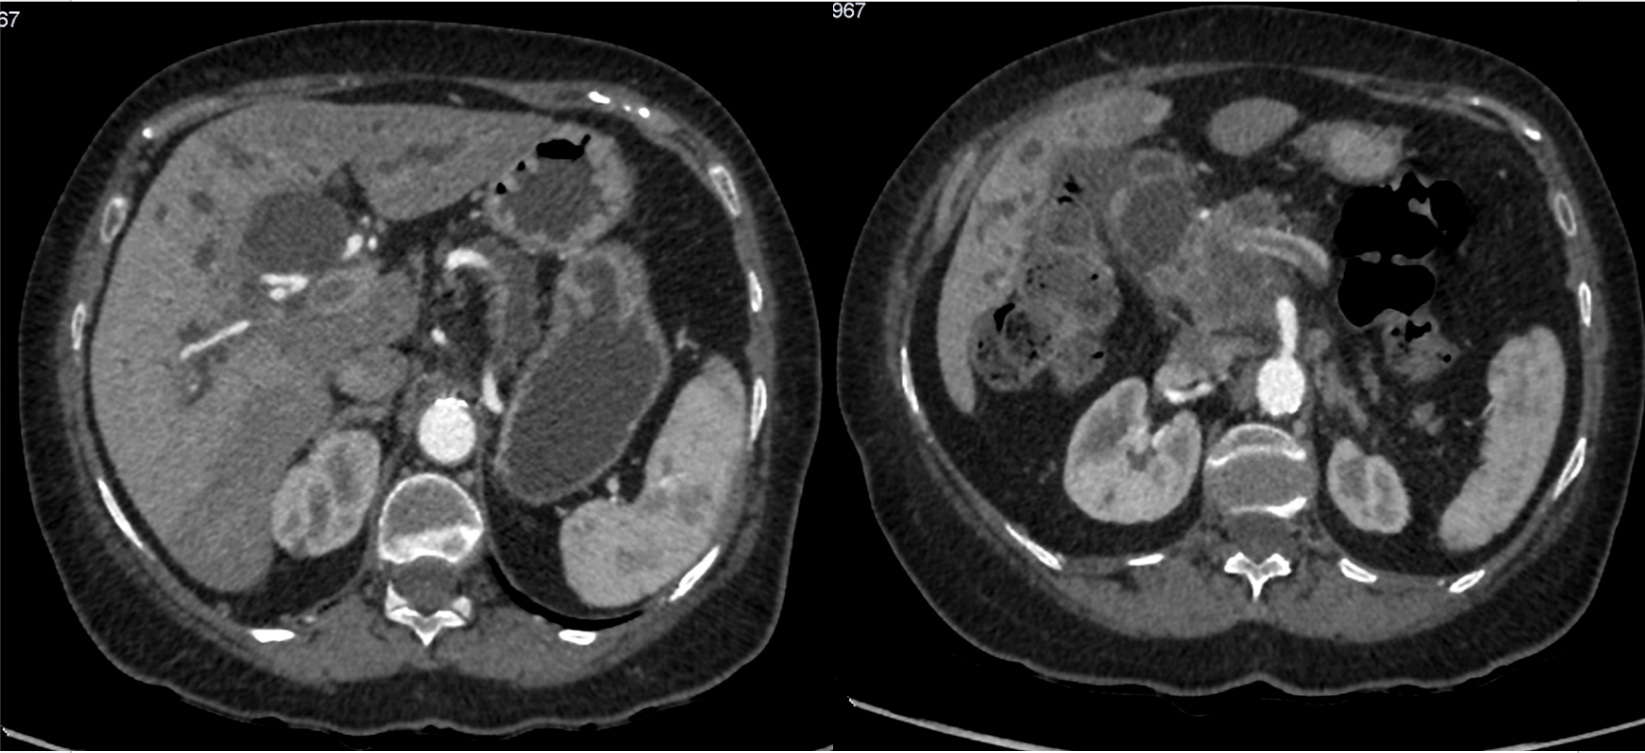

Ante la elevada sospecha de cáncer de páncreas el siguiente paso sería confirmarlo y estadificar el tumor, para ello el estándar de referencia es el TAC. La RM tiene mayor sensibilidad en caso de tumores pequeños y en la valoración de enfermedad a distancia. El PET no ha demostrado utilidad en la estadificación del carcinoma de páncreas, tan solo se usa para la valoración de metástasis en localizaciones insospechadas o bien para el seguimiento tras la cirugía.